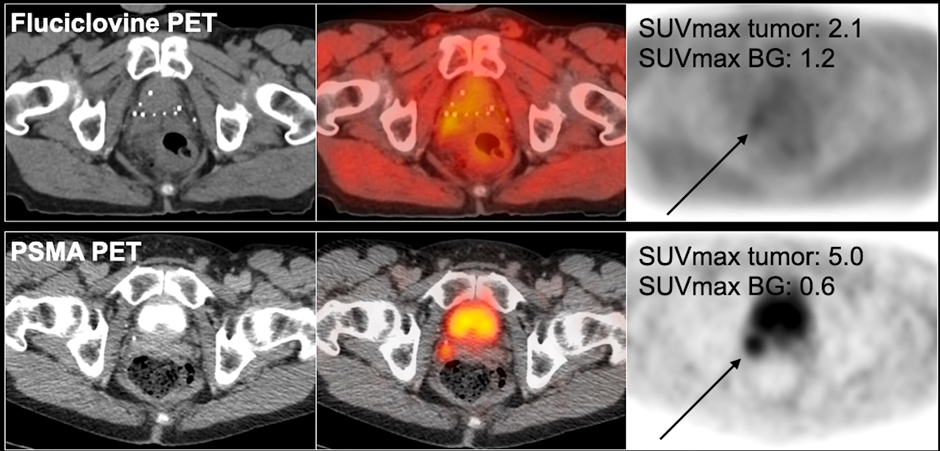

Understanding SUVmax

SUVmax refers to standardized uptake value maximum.

Higher SUV values may indicate:

- Increased tracer uptake

- Greater PSMA expression

- Higher suspicion for active disease

However, SUV interpretation must always be correlated with clinical context.